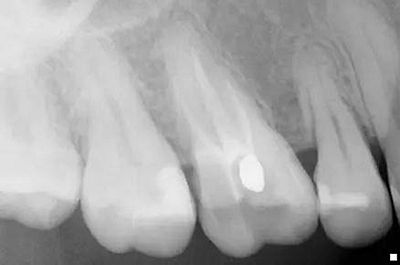

原始x线影像

X线摄片状况。